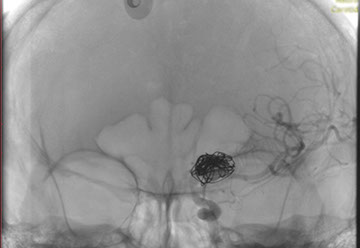

La paciente ingreso al Servicio de Hemodinamia el día martes 11 de febrero con un aneurisma cerebral gigante en la carótida izquierda y se le practicó una embolización; es decir una oclusión por dentro del mismo, donde se colocó un dispositivo denominado coils más un stent diversor de flujo. El procedimiento fue exitoso y contó con la colaboración de médicos neurointervencionistas del Instituto Oulton de la Ciudad de Córdoba.